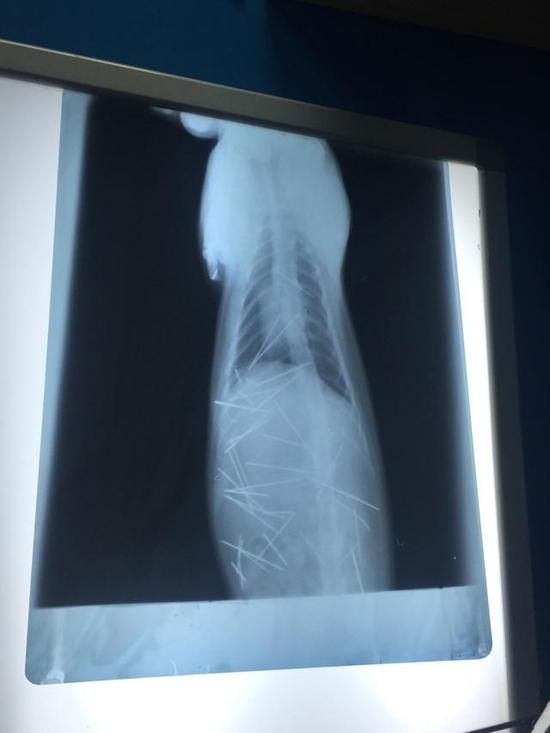

小猫体内被打入钢针

X光图片

这是一个残忍而又暖心的故事。一位小姑娘发现她收养一年的小猫脖子后有凸起,到医院检查发现,小猫体内有多达30至40根针。广州某宠物医生判断,这些针不是手工插入,很有可能是用类似气枪的东西打入的。5月21日夜,手术完成,医生用了近4小时的时间,取出了43根针(包括断掉的针头)。主人表示,很多针都已经生锈。

这位生活在深圳的小姑娘是5月19日发现小猫异常的,她在当晚发出的微博有多张小猫的X光照片,其中密密麻麻的针看起来十分恐怖。观察者网注意到,她的这条微博已有3万余次转发。次日(20日),她带小猫来到深圳某宠物医院治疗,因为该院没有C型臂,所以又转至广州一家宠物医院。21日夜手术结束后,该宠物医院表示,7根针是在皮肤或肌肉,3根针和2个断端在胸腔心脏旁边。30根针在腹腔,其中有4根是插入到左侧肾脏。这是一个复杂的手术,为了这个可怜猫猫,X线连续曝光53次。